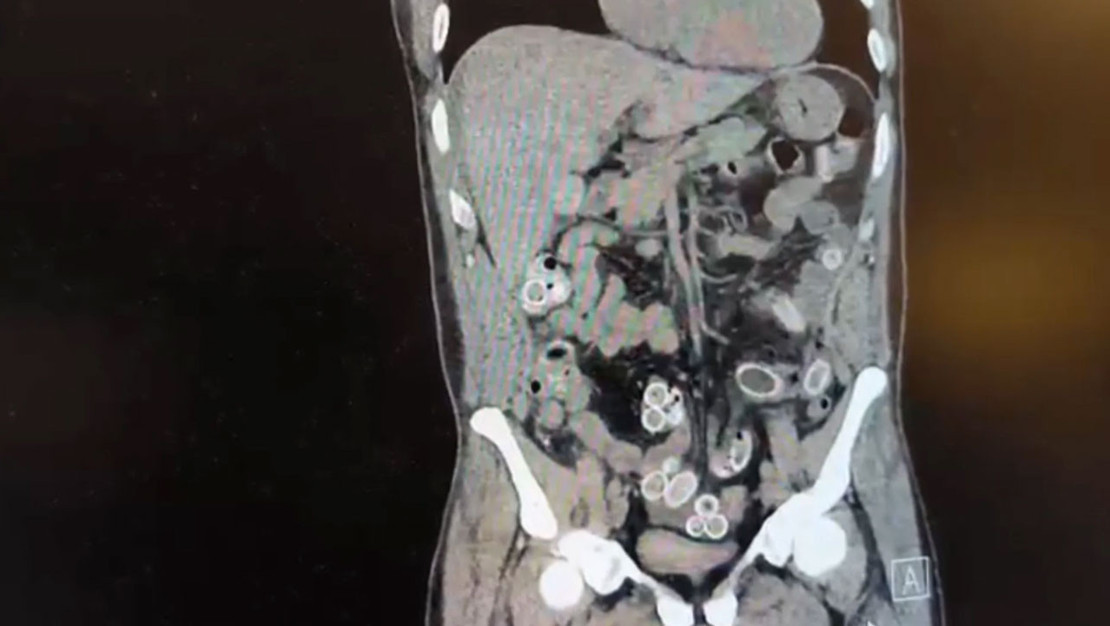

Beşiktaş’ta Fas’tan yaklaşık 3 bin kilometre mesafeden Türkiye’ye uçakla ulaşan Cüneyt Ç. (52), burada iki gün sonra mide ağrısı şikayetiyle Fulya’da yer alan özel bir hastaneye başvurdu. Yapılan muayene sonrası çekilen tomografide, Cüneyt Ç.’nin mide ve bağırsaklarında yabancı maddeler belirlendi. Ardından hastane, durumu polis ekiplerine iletti.

Doktorların yaptığı değerlendirme sonucunda ameliyata alınan Cüneyt Ç.’nin mide ve bağırsaklarından toplamda 49 adet esrar macunu kapsül halinde çıkarıldı. Bu kapsüllerin toplam ağırlığının 259,7 gram olduğu bildirildi. Şüpheliye ait bir cep telefonu da incelenmek üzere ilgili ekiplerce alındı.